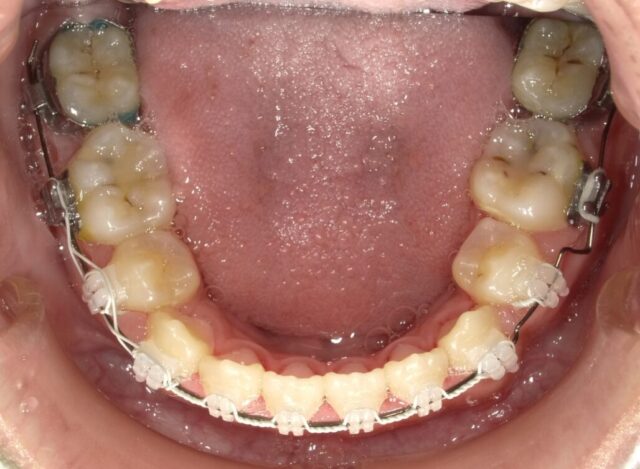

≪下顎咬合面観≫

2023年6月